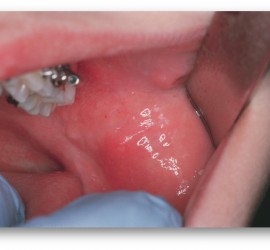

Аденокарцинома — злокачественные эпителиальные опухоли, образующие железистые и папиллярные структуры, но не имеющие характерных признаков других видов рака слюнных желез. Возникают как в больших, так и в малых слюнных железах. Гистологически связаны с протоками слюнных желез. Наиболее характерные морфологические признаки аденокарциномы слюнных желез — пролиферация эпителия в протоковых образованиях в виде […]